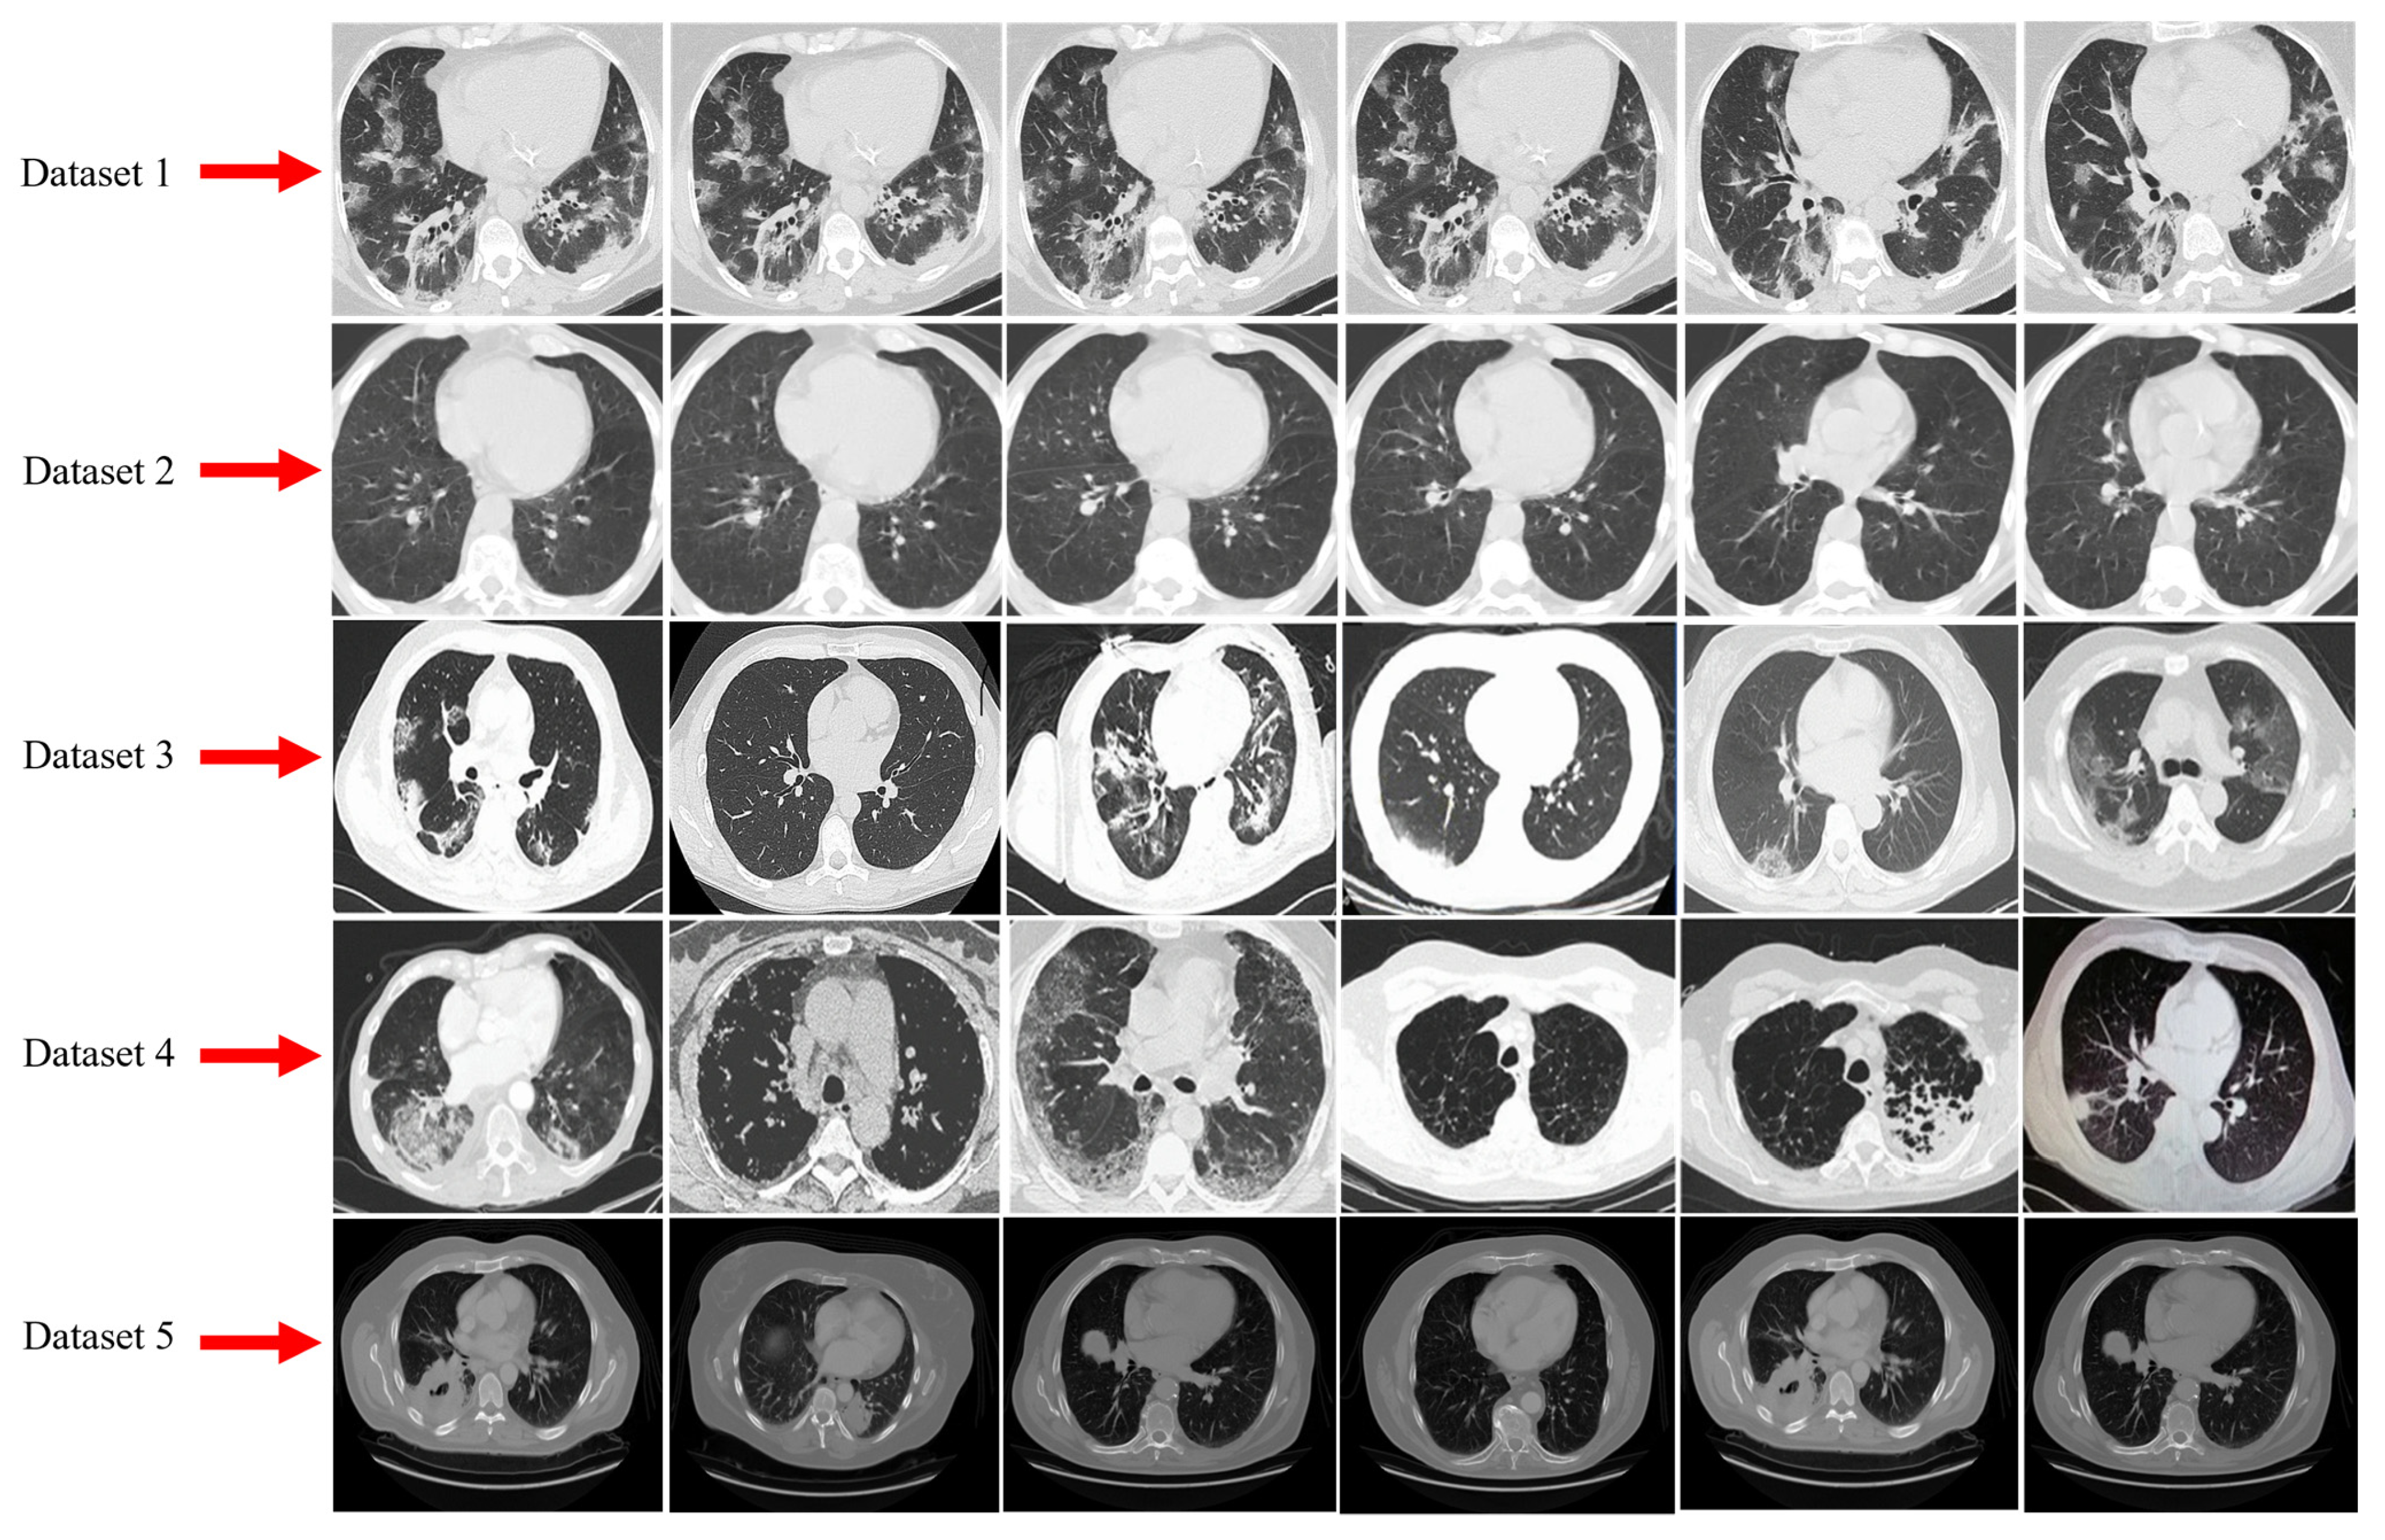

3.1. Dataset Description and Data Augmentation

3.1.1. Dataset-1

3.1.2. Dataset-2

3.1.3. Dataset-3

3.1.4. Dataset-4

3.1.5. Dataset-5

| Datasets | No. of Patients | COVID-19 CT Scans | Normal CT Scans | Image Format | Type of CT Scans | Total Number of CT Scans |

|---|---|---|---|---|---|---|

| Dataset 1 [56] | 1000 | 35,635 | 9367 | DICOM | 2D | 45,002 |

| Dataset 2 [57] | 89 | 28,395 | 5611 | PNG | 3D | 34,006 |

| Dataset 3 [58] | NA | 1252 | 1230 | PNG | 2D | 2482 |

| Dataset 4 [59] | 1110 | 125 | 254 | 3D CT scans | 3D | 379 |

| Dataset 5 [60] | 216 | 349 | 463 | PNG | 2D | 812 |